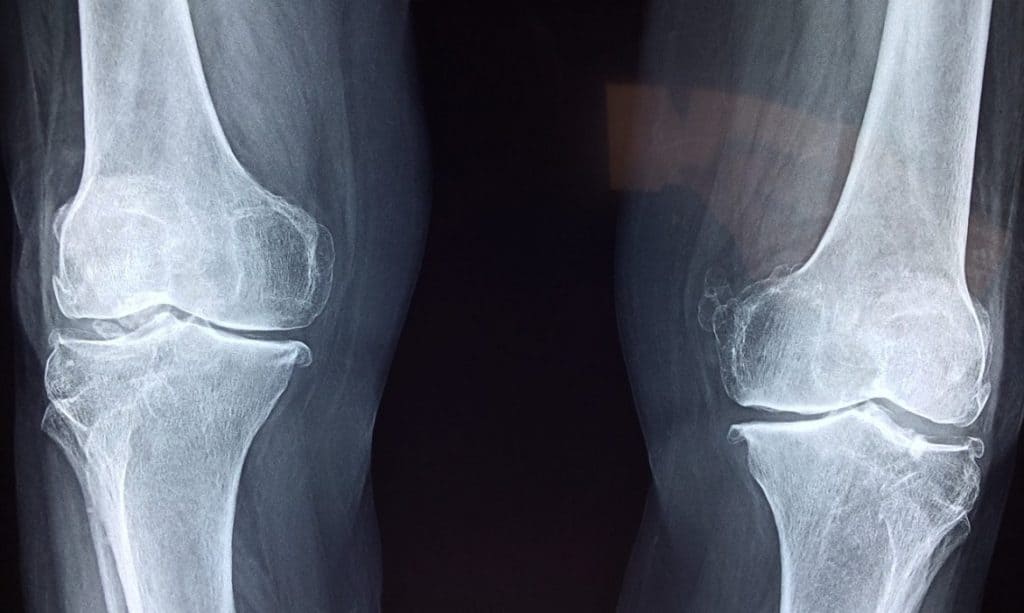

Do I need imaging?

X-rays can show narrowing of the joint space and bone changes with osteoarthritis, but this does not necessarily correlate with one’s symptoms or clinical presentation. This means that a person with mild changes on imaging may experience lots of pain and decreased range of motion, while another person with severe osteoarthritis on imaging may have good function. The Framington Osteoarthrits Study found radiographic (x-ray) presence of OA in 27% of those participants aged 65-69 years old; however only 11% of women and 7% of men had symptoms of OA. As well, of those with severe changes on x-ray, only 40% were symptomatic.5 Imaging can be helpful to show joint changes, but must be correlated with a clinical presentation - your pain levels, movement, and ability to do the activities that you enjoy.